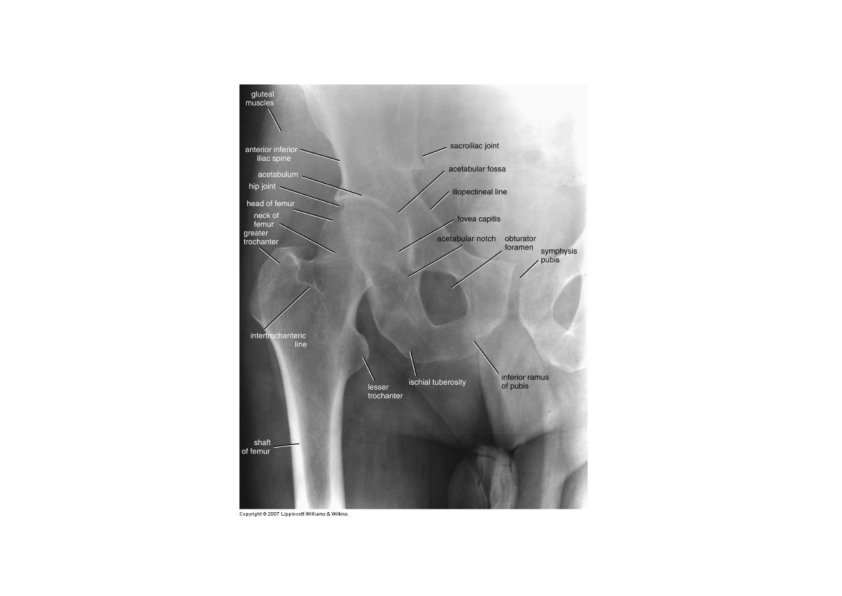

Pelvic (Hip) Girdle • Each coxal (hip) bone consists of three bones that fuse together: ilium, pubis, and ischium • The two coxal bones are joined anteriorly by the pubic symphysis (fibrocartilage) • Joined posteriorly by the sacrum forming the sacroiliac joints

Ilium • Largest of the three hip bones • Ilium is the superior part of the hip bone • Consists of a superior ala and inferior body which forms the acetabulum (the socket for the head of the femur) • Superior border ‐ iliac crest • Hip pointer ‐ occurs at anterior superior iliac spine • iliac spines • Greater sciatic notch ‐ allows passage of sciatic nerve • Iliac fossa for muscle attachment • Gluteal lines indicating muscle attachment • Sacroiliac joint at auricular surface & iliac tuberosity

Ischium and Pubis • Ischium ‐ inferior and posterior part of the hip bone • Most prominent feature is the ischial tuberosity, it is the part that meets the chair when you are sitting • ischial spine • lesser sciatic notch • ramus • Pubis ‐ inferior and anterior part of the hip bone • Superior and inferior rami and body

Surface Anatomy of Pelvic Girdle • Iliac crest • ASIS • Pubic symphysis • Pubic tubercle • 2 cm from pubic symphysis • Ischial tuberosity